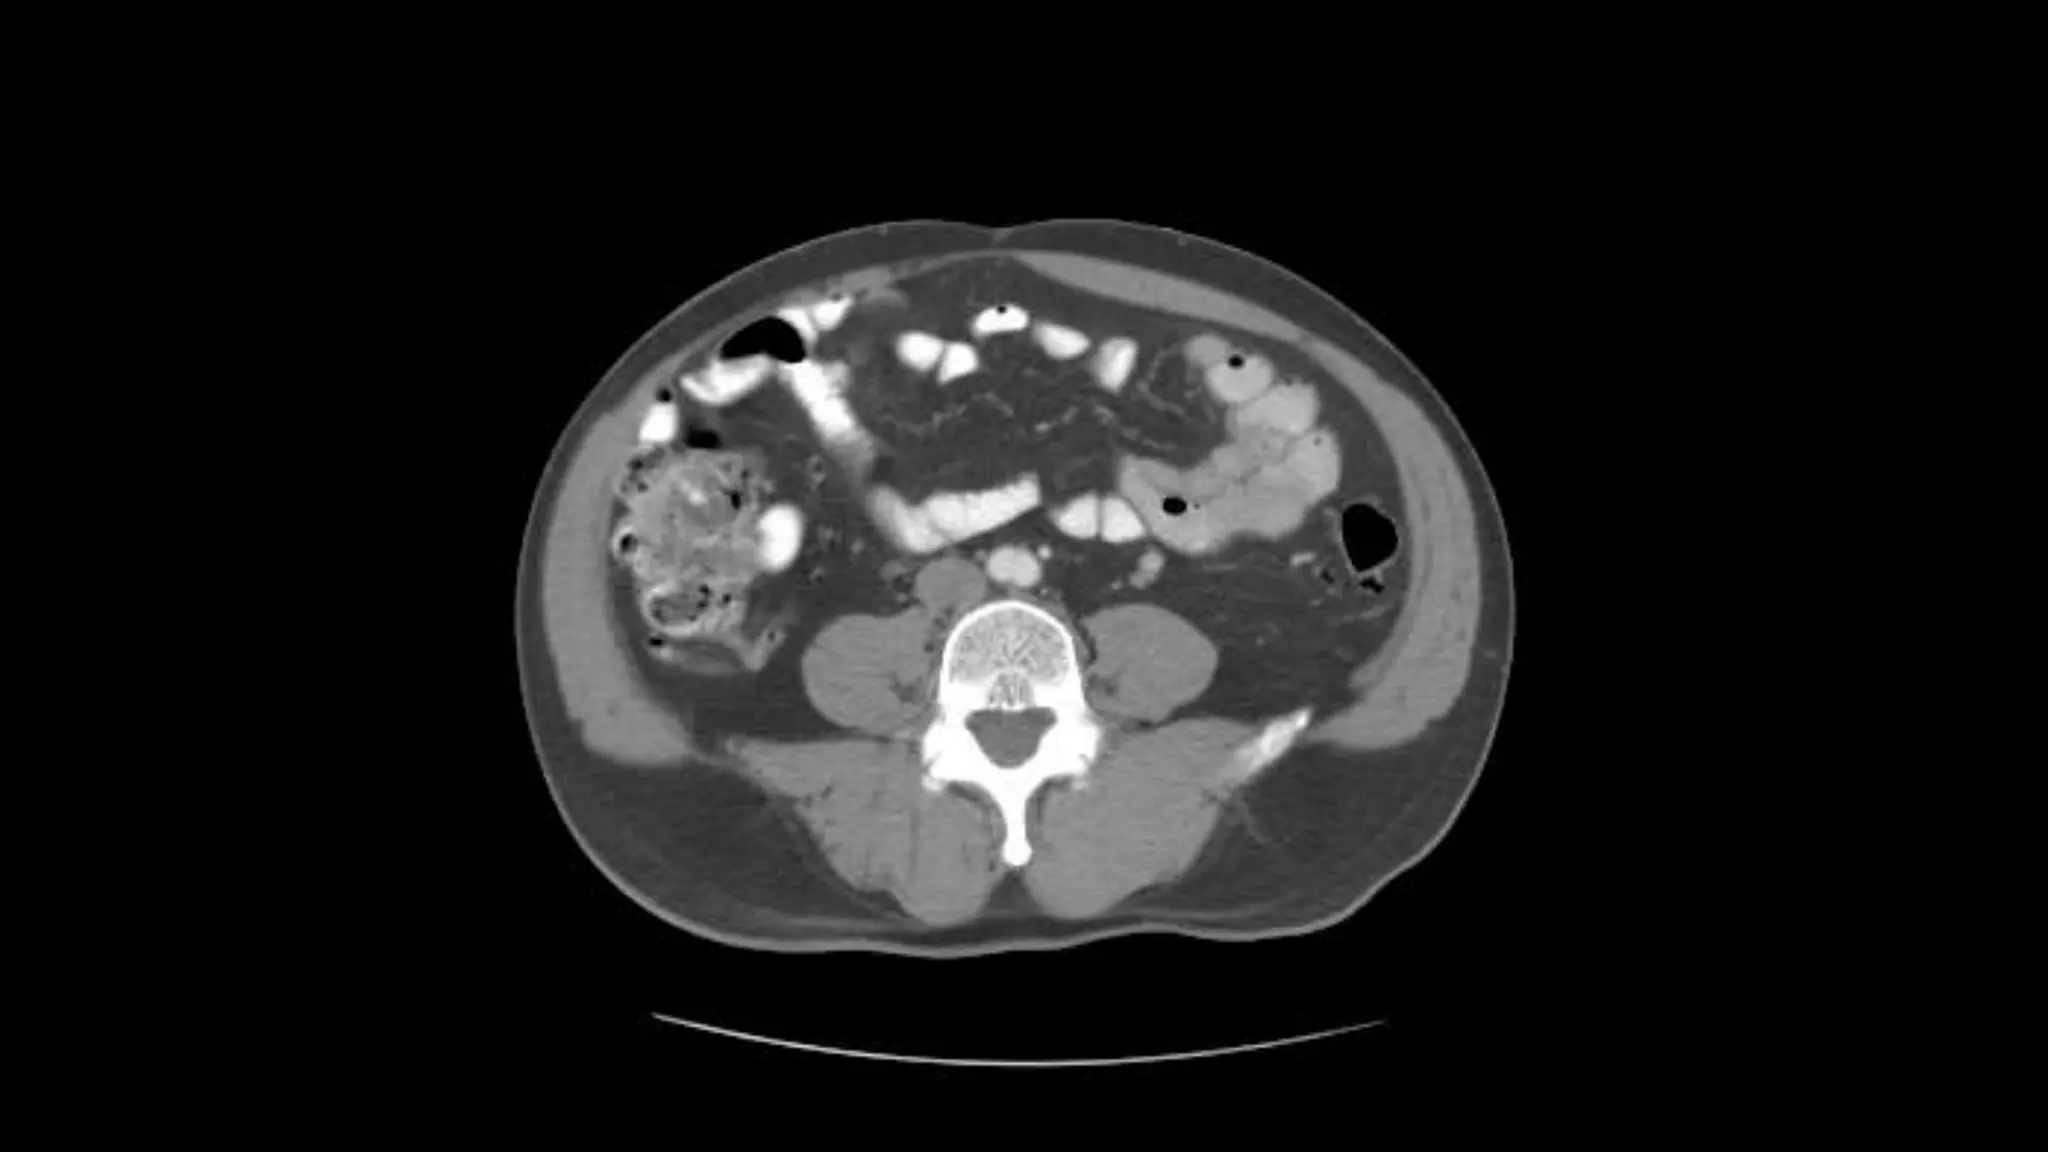

Note inferior mesentericartery emerging from aorta Inferior mesenteric vein extends cephalad to join smv.

Aorta bifurcates intocommon illiac arteries Appendix is noted coiling in Rt. Lower quadrant Note air in lumen on adjacent scans Psoas muscles